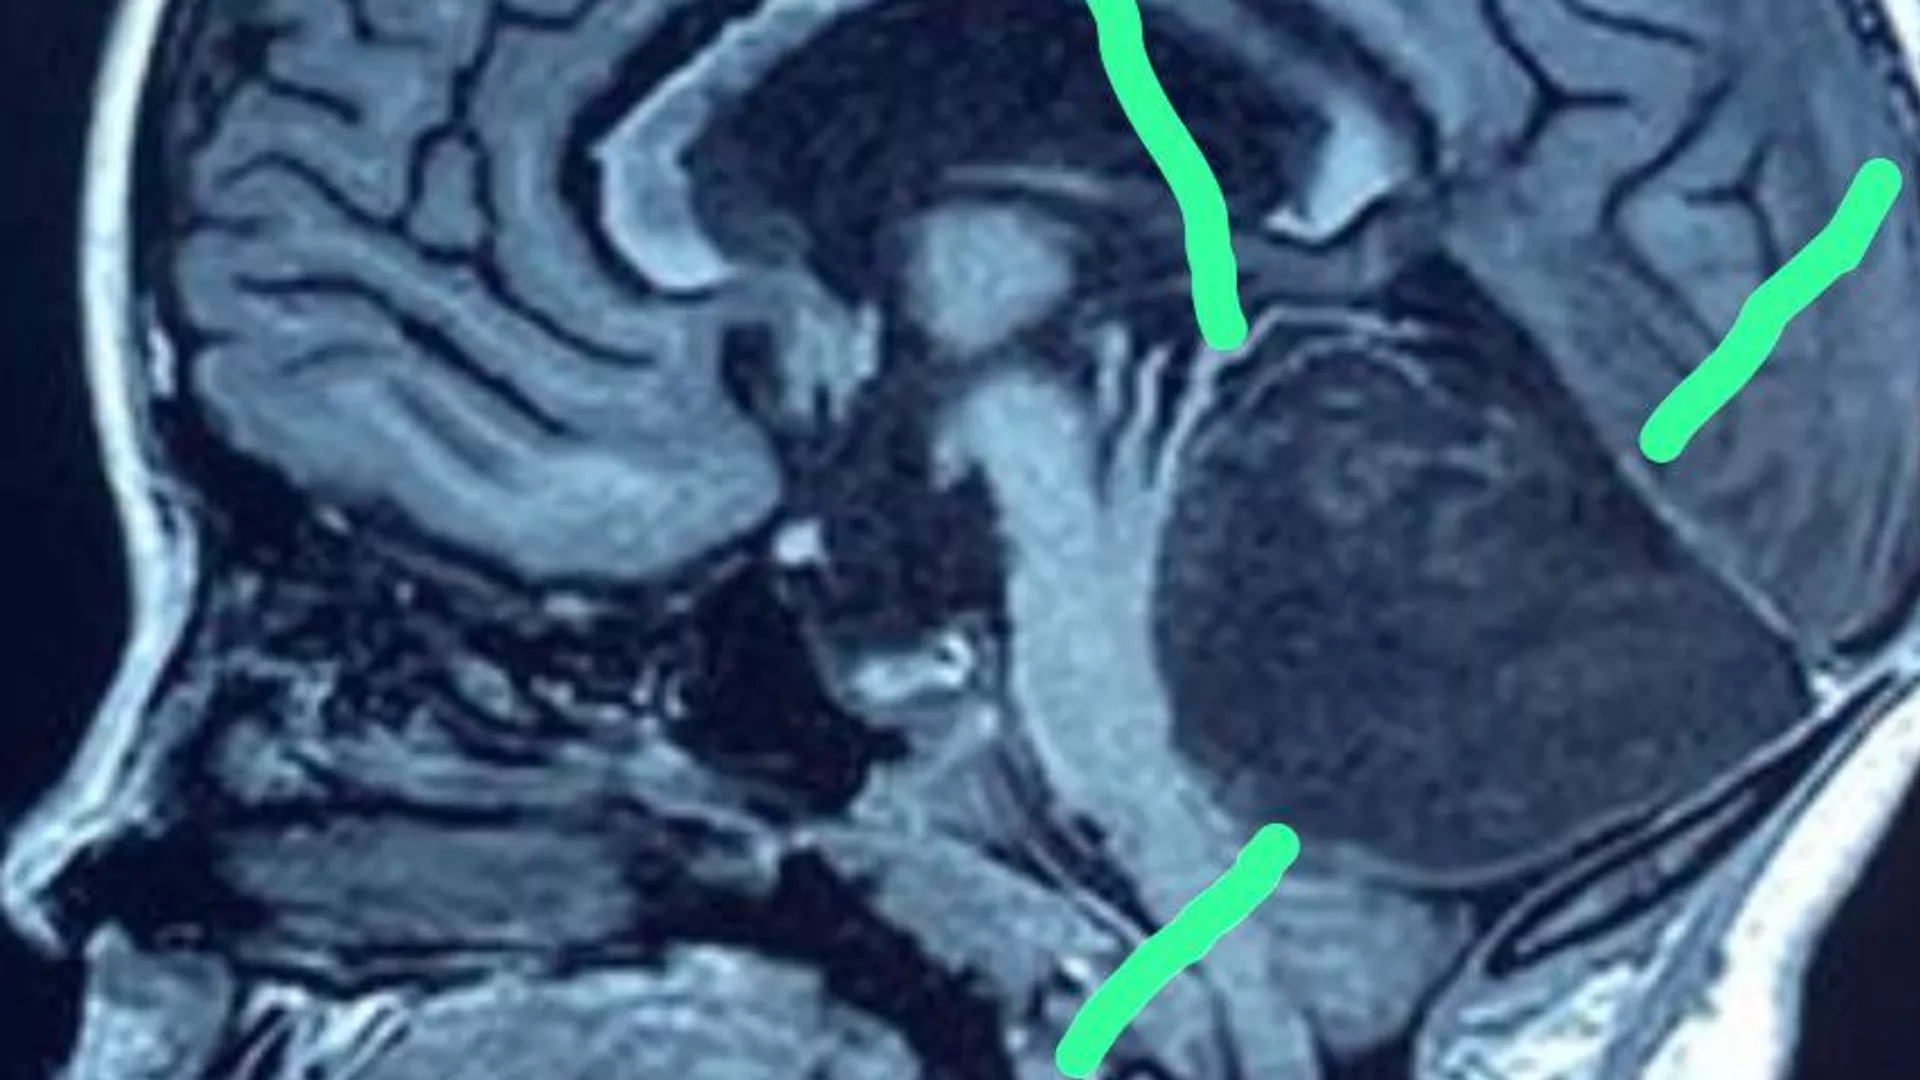

БИШКЕК, 11 апр — Sputnik. В отделении нейрохирургии Национального центра охраны материнства и детства (НЦОМиД) выполнена уникальная операция на головном мозге — удалили клок волос, сообщает пресс-служба Минздрава.

Операцию провели академик Национальной академии наук, профессор Миталип Мамытов и врачи отделения нейрохирургии во главе с заведующим отделением Бакытом Карачевым.

У восьмилетней жительницы Джалал-Абадской области Т. А. было диагностировано объемное образование на дне 4-го желудочка головного мозга.

"Операция по удалению опухоли — тератомы дна 4-го желудочка головного мозга — прошла успешно. Содержимым тератомы был клок волос, который рос, по-видимому, всю жизнь ребенка до поступления в НЦОМиД", — говорится в сообщении.

Возможно, патология связана с нарушением внутриутробного развития. Продолжение роста волос угрожало здоровью пациентки.